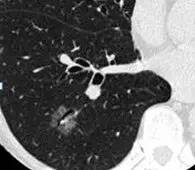

2. 马赛克灌注(Mosaic perfusion)

这是肺内通气灌注不一致的表现,主要是小支气管炎症导致肺内局部积气,像马赛克拼图一样